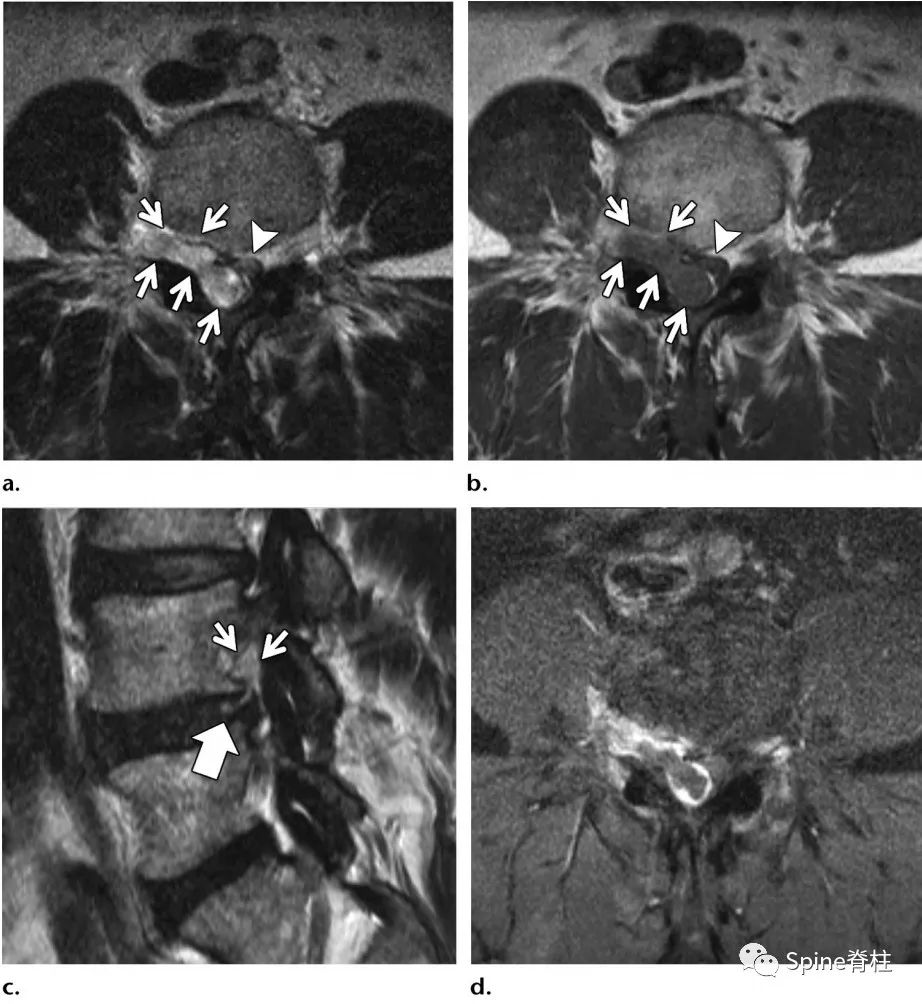

60岁,男性患者,因进行性、严重的接近L5根支配区的下肢放射痛3周入院,诊断为背侧硬膜外椎间盘突出症。

腰椎间盘突出症状表现,腰椎间盘突出症疼痛最佳止痛方法

L2-L3水平背侧硬膜外占位,磁共振增强提示病灶边缘强化(c)

背侧硬膜外椎间盘突出示意图

突出的椎间盘迁移至硬膜外后间隙,硬膜外背侧和腹外侧均有异常软组织(椎间盘内容物或肉芽组织)。L3-4是最常见的节段,其次是L4-5。

背侧硬膜外椎间盘突出症(dorsal epidural disk herniation)常发生在常L3-4,其次为L4-5,易误诊为滑膜囊肿、血肿、脓肿或肿瘤。常急性发病且常伴发马尾神经综合征。